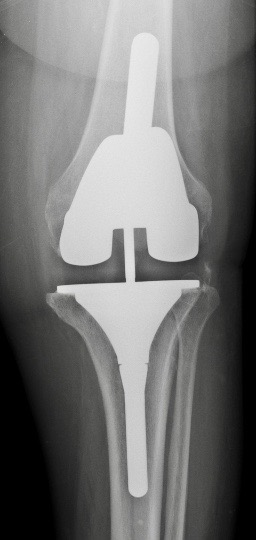

A. PTG à glissement +/- bouton patellaire

le plus couramment utilisé

pour les déformations petites et moyennes

remplace les ligaments croisés

Les ligaments latéraux doivent être en bon état pour assurer une bonne stabilité.